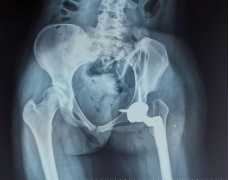

通过小张的骨盆X线可以看到,她的左侧髋臼是一个发育不良的状态,髋臼较小较浅,外展角较大,而股骨头已经完全脱位,根据脱位高度分型为DDH(developmental dysplasia hip,发育性髋关节发育不良)IV型,已经属于最严重的程度了。

(下肢不等长,Allis征+) (骨盆正位片)